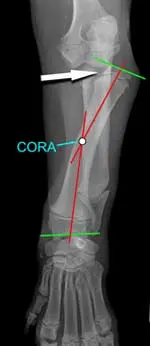

The apex of the deformity, or the center of rotation of angulation (CORA), is at the approximate midpoint of the diaphysis of the radius. The radial head is slightly misshapen from the contact pressure of the humeral capitulum (Figure 2).

Figure 2: Frontal plane radiograph of the left antebrachium. Green lines represent joint orientation lines; red lines represent the anatomic axes of the proximal and distal segments of the radius. Whereas a normal canine radius should possess a single anatomic axis in the frontal plane, the intersection of these 2 axes demonstrates the location of the apex of the deformity, also referred to as the center of rotation of angulation. Note the misshapen radial head that is caudolaterally displaced (white arrow).